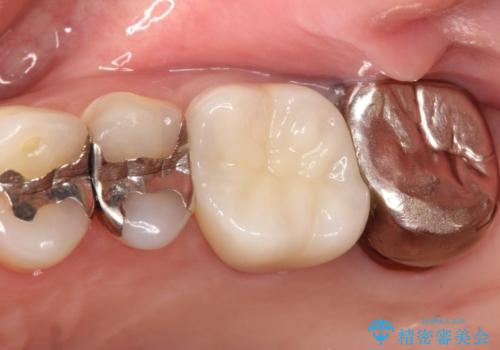

【再根管治療】オールセラミッククラウンによる修復

- 治療途中の歯があることを主訴に来院されました。

根管治療を行なったのちオールセラミックにて修復治療を行なっております。

第二大臼歯の治療は希望されませんでした。